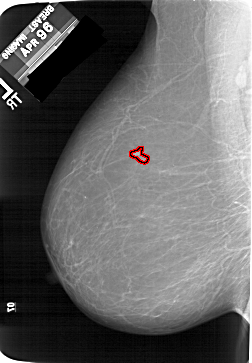

A_1204_1.LEFT_MLO

LEFT_MLO LINES 6526 PIXELS_PER_LINE 4531 BITS_PER_PIXEL 12 RESOLUTION 43.5 OVERLAY

FILE: A_1204_1.LEFT_MLO.OVERLAY

TOTAL_ABNORMALITIES 1

ABNORMALITY 1

LESION_TYPE MASS SHAPE IRREGULAR MARGINS ILL_DEFINED

ASSESSMENT 4

SUBTLETY 3

PATHOLOGY MALIGNANT

TOTAL_OUTLINES 1

BOUNDARY